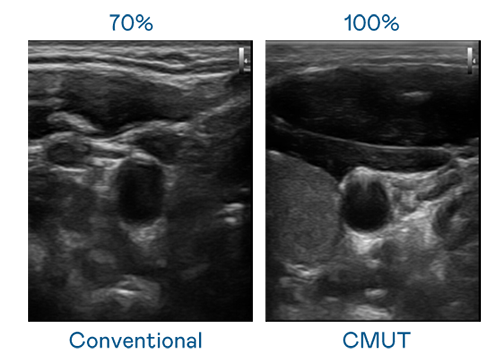

CMUT 技术是一种用电容式微机电元件来产生超音波讯号的技术。与传统 PZT 压电式技术相比,CMUT 频宽增加 30%,更宽频的超音波讯号让影像解析度大幅提升,是实现高影像品质医疗超音波扫描、促进精准医疗发展的关键技术。

大频宽带来超清晰影像

超音波影像的解析度高低,首先取决于探头能发出的讯号频宽。d88尊龙z6 CMUT 可提供高清晰的超音波讯号,提供高频宽、高灵敏度、影像纹理细节更高的超音波影像,协助医护人员缩短影像判读时间及利用精准的医疗影像进行诊断。